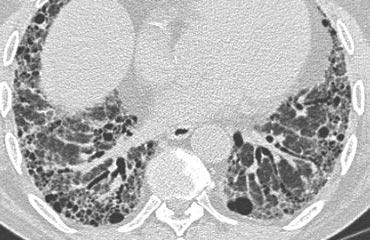

Bên trái là một trường hợp có nhiều nang hình tròn và hình dạng kỳ lạ.

Tổn thương chiếm ưu thế ở thùy trên.

Bệnh nhân có tiền sử hút thuốc lá lâu dài.

Sự kết hợp các dấu hiệu này điển hình cho bệnh mô bào Langerhans.

Bệnh mô bào tế bào Langerhans (LCH) là một bệnh vô căn, đặc trưng ở giai đoạn sớm bởi các nốt u hạt chứa mô bào Langerhans và bạch cầu ái toan.

Ở giai đoạn muộn hơn, các u hạt được thay thế bởi xơ hóa và hình thành các nang.

Đây là một tình trạng không phổ biến.

Phần lớn bệnh nhân là người trẻ hoặc trung niên, biểu hiện với các triệu chứng không đặc hiệu như ho và khó thở. Có đến 20% bệnh nhân biểu hiện bằng tràn khí màng phổi và hơn 90% bệnh nhân là người hút thuốc lá.

Hầu hết các nang có hình tròn, nhưng cũng có thể có hình dạng bất thường (hình thùy đôi hoặc hình lá ba thùy).

Sự chiếm ưu thế ở thùy trên về kích thước và số lượng nang là phổ biến.

Bên trái là một trường hợp có nhiều nang phân bố đều khắp phổi (trái ngược với LCH).

Lưu ý tình trạng tràn khí màng phổi.

Bệnh nhân không có tiền sử hút thuốc và là nữ giới 40 tuổi.

Sự kết hợp các dấu hiệu này điển hình cho Bệnh U Cơ Bạch Huyết (LAM).

Bệnh u cơ bạch huyết là một bệnh hiếm gặp đặc trưng bởi sự tăng sinh tiến triển của các tế bào hình thoi, giống với cơ trơn.

Sự tăng sinh của các tế bào này dọc theo các tiểu phế quản dẫn đến hiện tượng bẫy khí và hình thành các nang phổi thành mỏng.

Vỡ các nang này có thể gây ra tràn khí màng phổi.

Các biểu hiện khác của LAM bao gồm bệnh hạch và tràn dịch màng phổi.

U cơ mạch bạch huyết chỉ xảy ra ở phụ nữ, thường trong độ tuổi sinh đẻ, từ 17 đến 50 tuổi.

Các biến đổi lâm sàng, X-quang và bệnh lý phổi tương tự được thấy ở khoảng 1% bệnh nhân mắc bệnh xơ cứng củ.

Hầu hết bệnh nhân tử vong trong vòng 10 năm kể từ khi khởi phát triệu chứng.